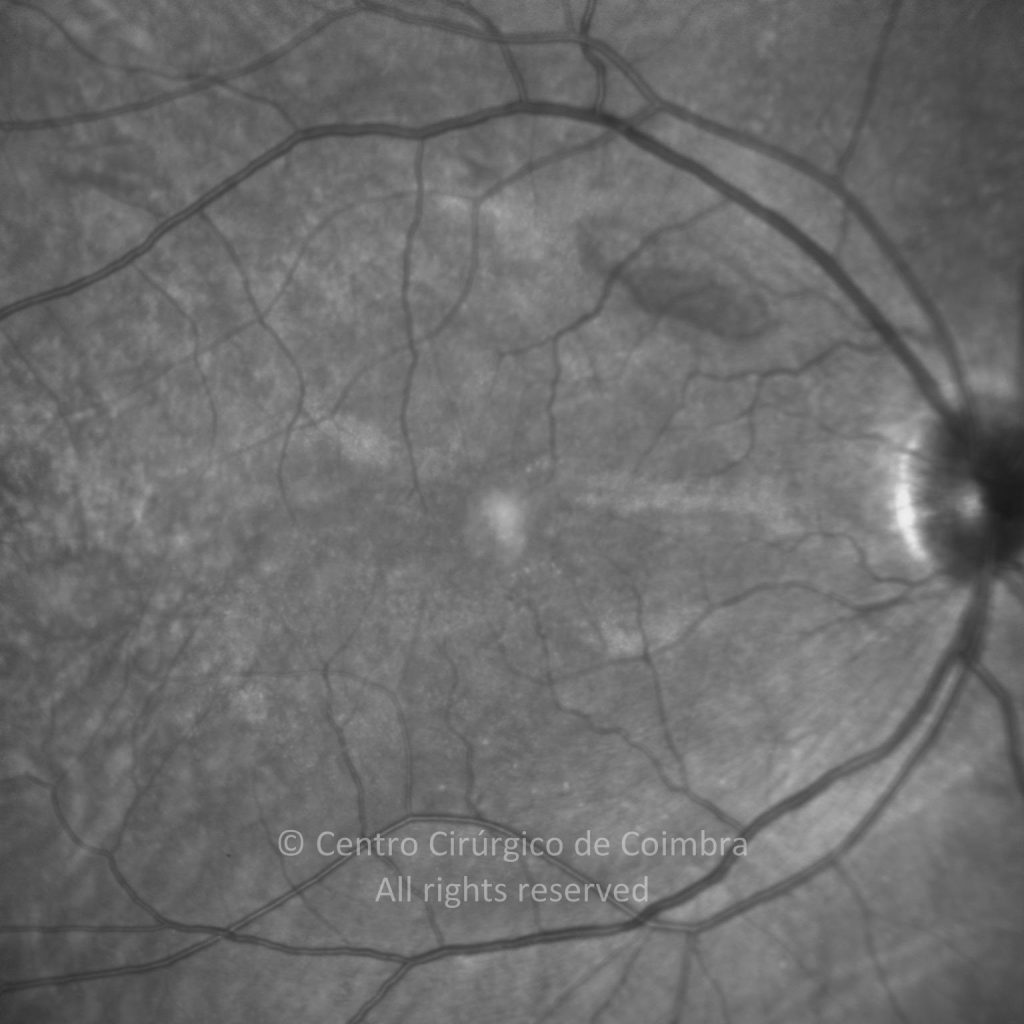

Paciente de 37 años con traumatismo contundente y ruptura del globo ocular. Presenta ruptura esclero-uveal, hifema, hemovítreo, desgarro periférico y temporal de la retina, hemorragias subretinianas y múltiples desprendimientos serosos.

MAVC: 20/25 OD, nueve años después de las cirugías (sutura escleral de la desinserción del músculo recto externo, vitrectomía posterior y fotocoagulación láser en el borde del desgarro retiniano, desprendimiento de retina inferior con proliferación vitreorretiniana y líquido subretiniano con algo de sangre; peeling de la membrana epirretiniana y maculorrexis de la MLI).